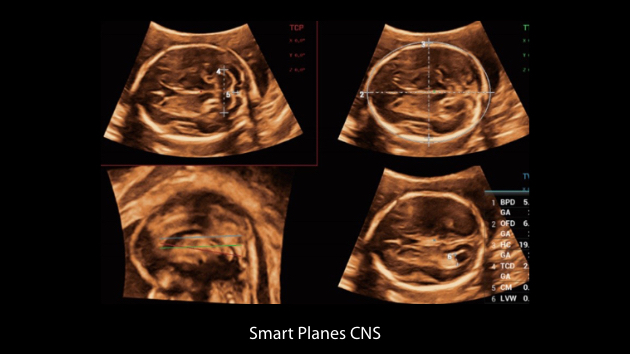

Obrazy kliniczne